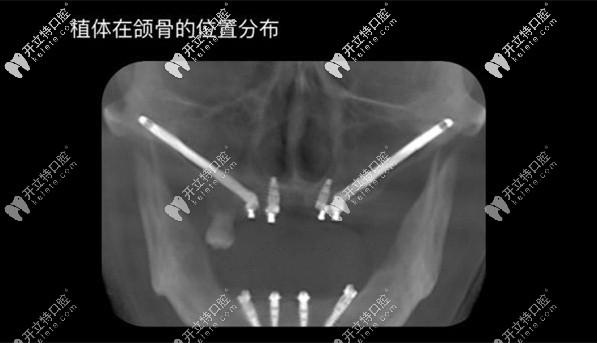

穿顴穿翼種植的全景片效果圖

種植體在頜骨的位置分布圖